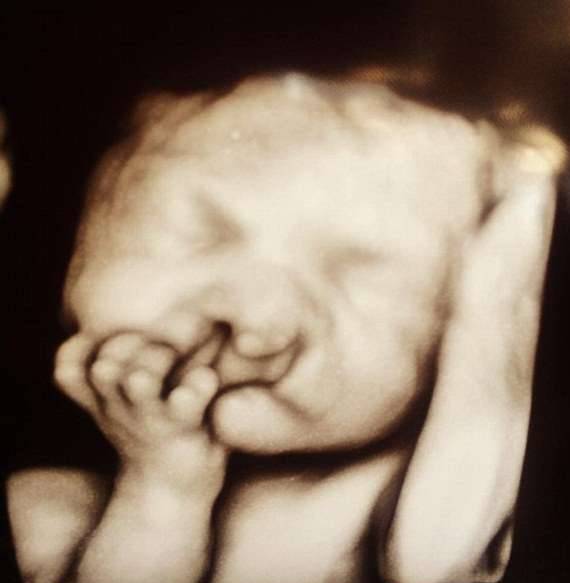

▼莎拉跟丈夫克里斯(Chris Eidam)从得知怀孕消息时,就感到非常高兴,因为他们一直期盼着有个宝宝。然而,在做例行的超音波检查时,医生却提出了一个问题。

▼医生表示,从超音波看起来,宝宝明显有着缺陷,代表发育状况不全,可能会影响他未来的生活。医生询问夫妻俩要不要留下宝宝,莎拉跟克里斯都决心把孩子生下,并认为不管未来有什幺阻碍,他们都会一起克服,「我们只希望儿子能平安地来到这世界,这样就够了。」